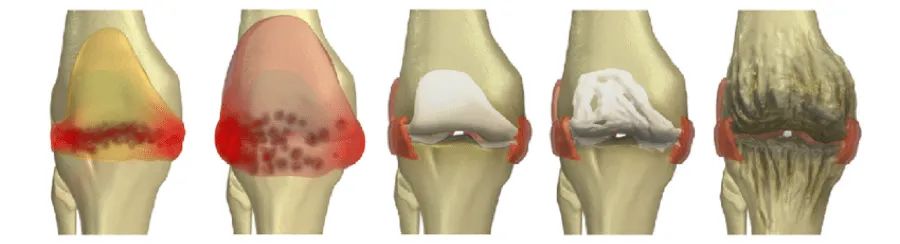

初期X线片观察不到关节腔内的出血改变而不能提供有力的诊断依据,而超声或磁共振可以观察到关节腔内出血,但血友病出血的严重程度与出血持续时间成正比,应以临床判断为主,不要等待影像学检查证据而耽误治疗。大量出血或反复出血以后,红细胞中的铁沉积在关节滑膜中,造成滑膜的增生以及滑膜内毛细血管的增生,进而导致滑膜炎。增生的滑膜内炎性细胞产生的酶和细胞因子会破坏关节软骨和骨,导致关节间隙变窄。各种原因引起的疼痛和关节病变导致患者关节活动受限、关节周围肌肉萎缩,关节挛缩、变形,最后发生发展为血友病性关节炎。

02 血友病性关节炎的分期

国际上将血友病性关节炎分为三期,大家可以详细看看:

Ⅰ期——出血期:

关节内突然急性出血伴有剧痛,关节出现明显的肿胀,皮肤温度升高,按压会有明显的疼痛,运动受限,关节呈保护性僵直状态。此时切记不能进行穿刺或切开,否则有致命危险,血肿吸收缓慢,需3~6周。

Ⅱ期——炎症期:

关节内反反复复的出血,关节肿胀更加明显、甚至走路受到限制,在运动的时候要会听到关节处的摩擦音。

Ⅲ期——退变期:

关节运动严重受限,肌肉萎缩,在膝关节多出现畸形,甚至严重致残。